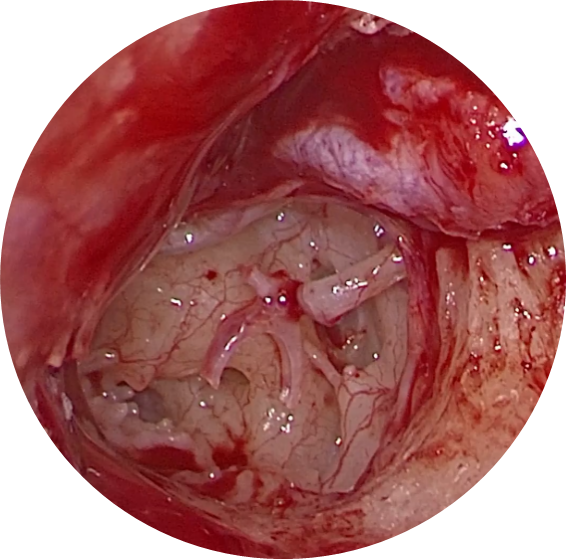

Vue endoscopique peropératoire de l’oreille moyenne (tympan soulevé) :

- Enclume

- Etrier (bloqué)